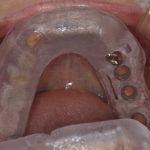

①お口の中の情報(レントゲンやお口の歯型の模型)を採得します

②採得した模型から理想の位置のかみ合わせを決めます

③そのかみ合わせと資料をコンピュータ上で合わせてインプラントを埋める位置を逆算します

④逆算したデータをもとに手術道具をオーダーメードで製作します

⑤実際に手術を行います

となります

(※一連の写真は全て同一のオペのものではありません)